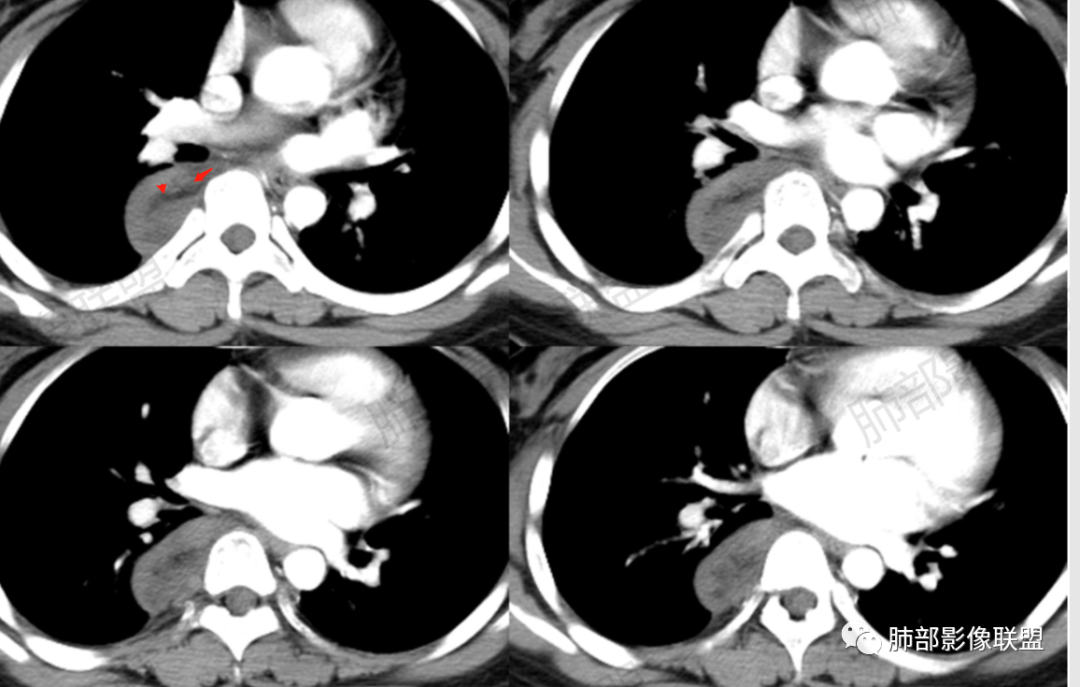

2.右后纵隔脊柱旁上下方向贴伏块影,“肾”形外观,边界清晰,密度不均,中央区域见脂肪密度影引向椎体前方,未见液性密度管腔影及钙化。

3.块影血供动脉来自肋间动脉,且由内后方侧入,其与下腔静脉之间未见回流通道。血管未见破坏,相邻组织未见侵入。

4.块影未延伸至椎管内,未见椎间孔扩大或骨质吸收破坏。

5.轻度渐进性强化。

1.肿块未横向经椎间孔延入椎管,或形成所谓“哑铃状”外观等,没有显示出沿脊神经根生长特征。长轴顺脊柱贴行恰好与交感神经路径相一致。

临床也缺乏及神经根压迫相关表现,因此来自脊神经根的神经鞘瘤几乎可以排除。

2.肿块含脂肪等成分,与交感神经路径相一致,渐进性轻度强化(可能含有粘液成分)等,以节细胞神经瘤最可能!尽管未显示“习惯性”的钙化。